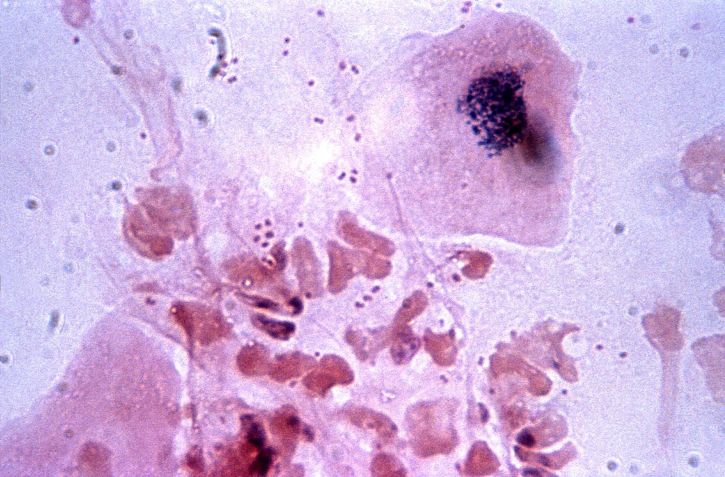

백혈구 수치가 낮아질 경우, 면역력 저하와 관련된 다양한 증상이 나타날 수 있습니다. 특히 구내염, 후두염, 림프절 염증 등의 감염이 잘 발생합니다. 림프절은 백혈구가 모여서 외부의 병원균과 싸우는 장소인데, 백혈구 수치가 부족할 경우 이곳에서 감염이 쉽게 발생할 수 있습니다. 면역력이 약해지면 발열, 고열, 설사와 같은 증상이 나타나기도 하며, 이는 신체가 감염과 싸우고 있음을 나타냅니다.

또한, 백혈구 수치가 낮아지면 신체의 염증 반응이 증가하게 됩니다. 이로 인해 몸이 붓거나 통증을 느끼는 경우가 많으며, 심한 경우에는 다른 질병으로 발전할 위험도 있습니다. 따라서 백혈구 수치가 낮은 경우에는 정기적인 건강 검진과 함께 전문가의 조언을 받는 것이 중요합니다.